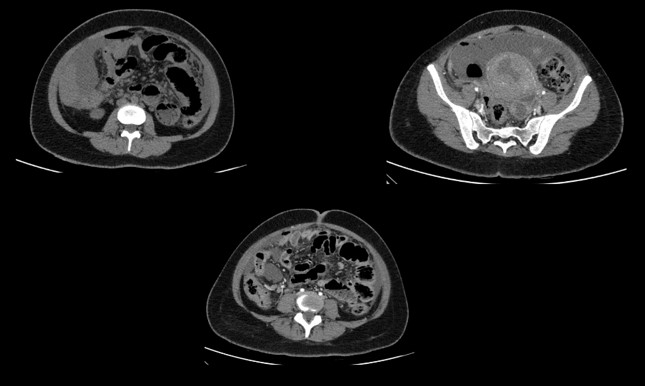

CECT ABDOMEN AND PELVIS - DAY 1

• A. Mild pneumoperitoneum. Few heterogeneously enhancing fibroids seen. Tubular hypodense area in left adnexa - likely pyosalpinx Diffuse greater omental fat stranding and peritoneal thickening - suggestive of peritonitis.